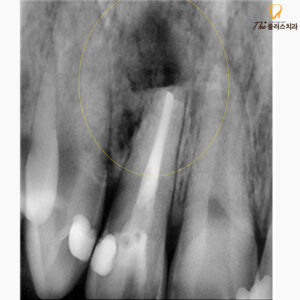

사진은 치근단 절제술이 완료된 후의

엑스레이 사진입니다.

깨끗하게 염증조직들을 제거하였으며,

뿌리 끝에 세균이 다시 감염되지 않도록

꼼꼼히 충전하여 마무리하였습니다.